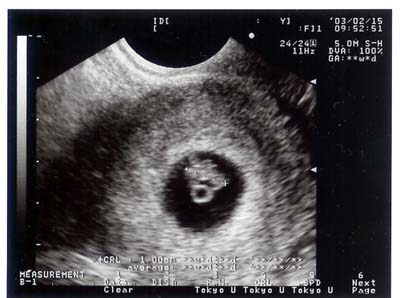

平成15年2月15日(土) 7週目

心臓が動いているのがわかる。

1cm、まだ頭もわからないって。

すべて正常。

豆粒の様な生命。

動いているのがわかる。